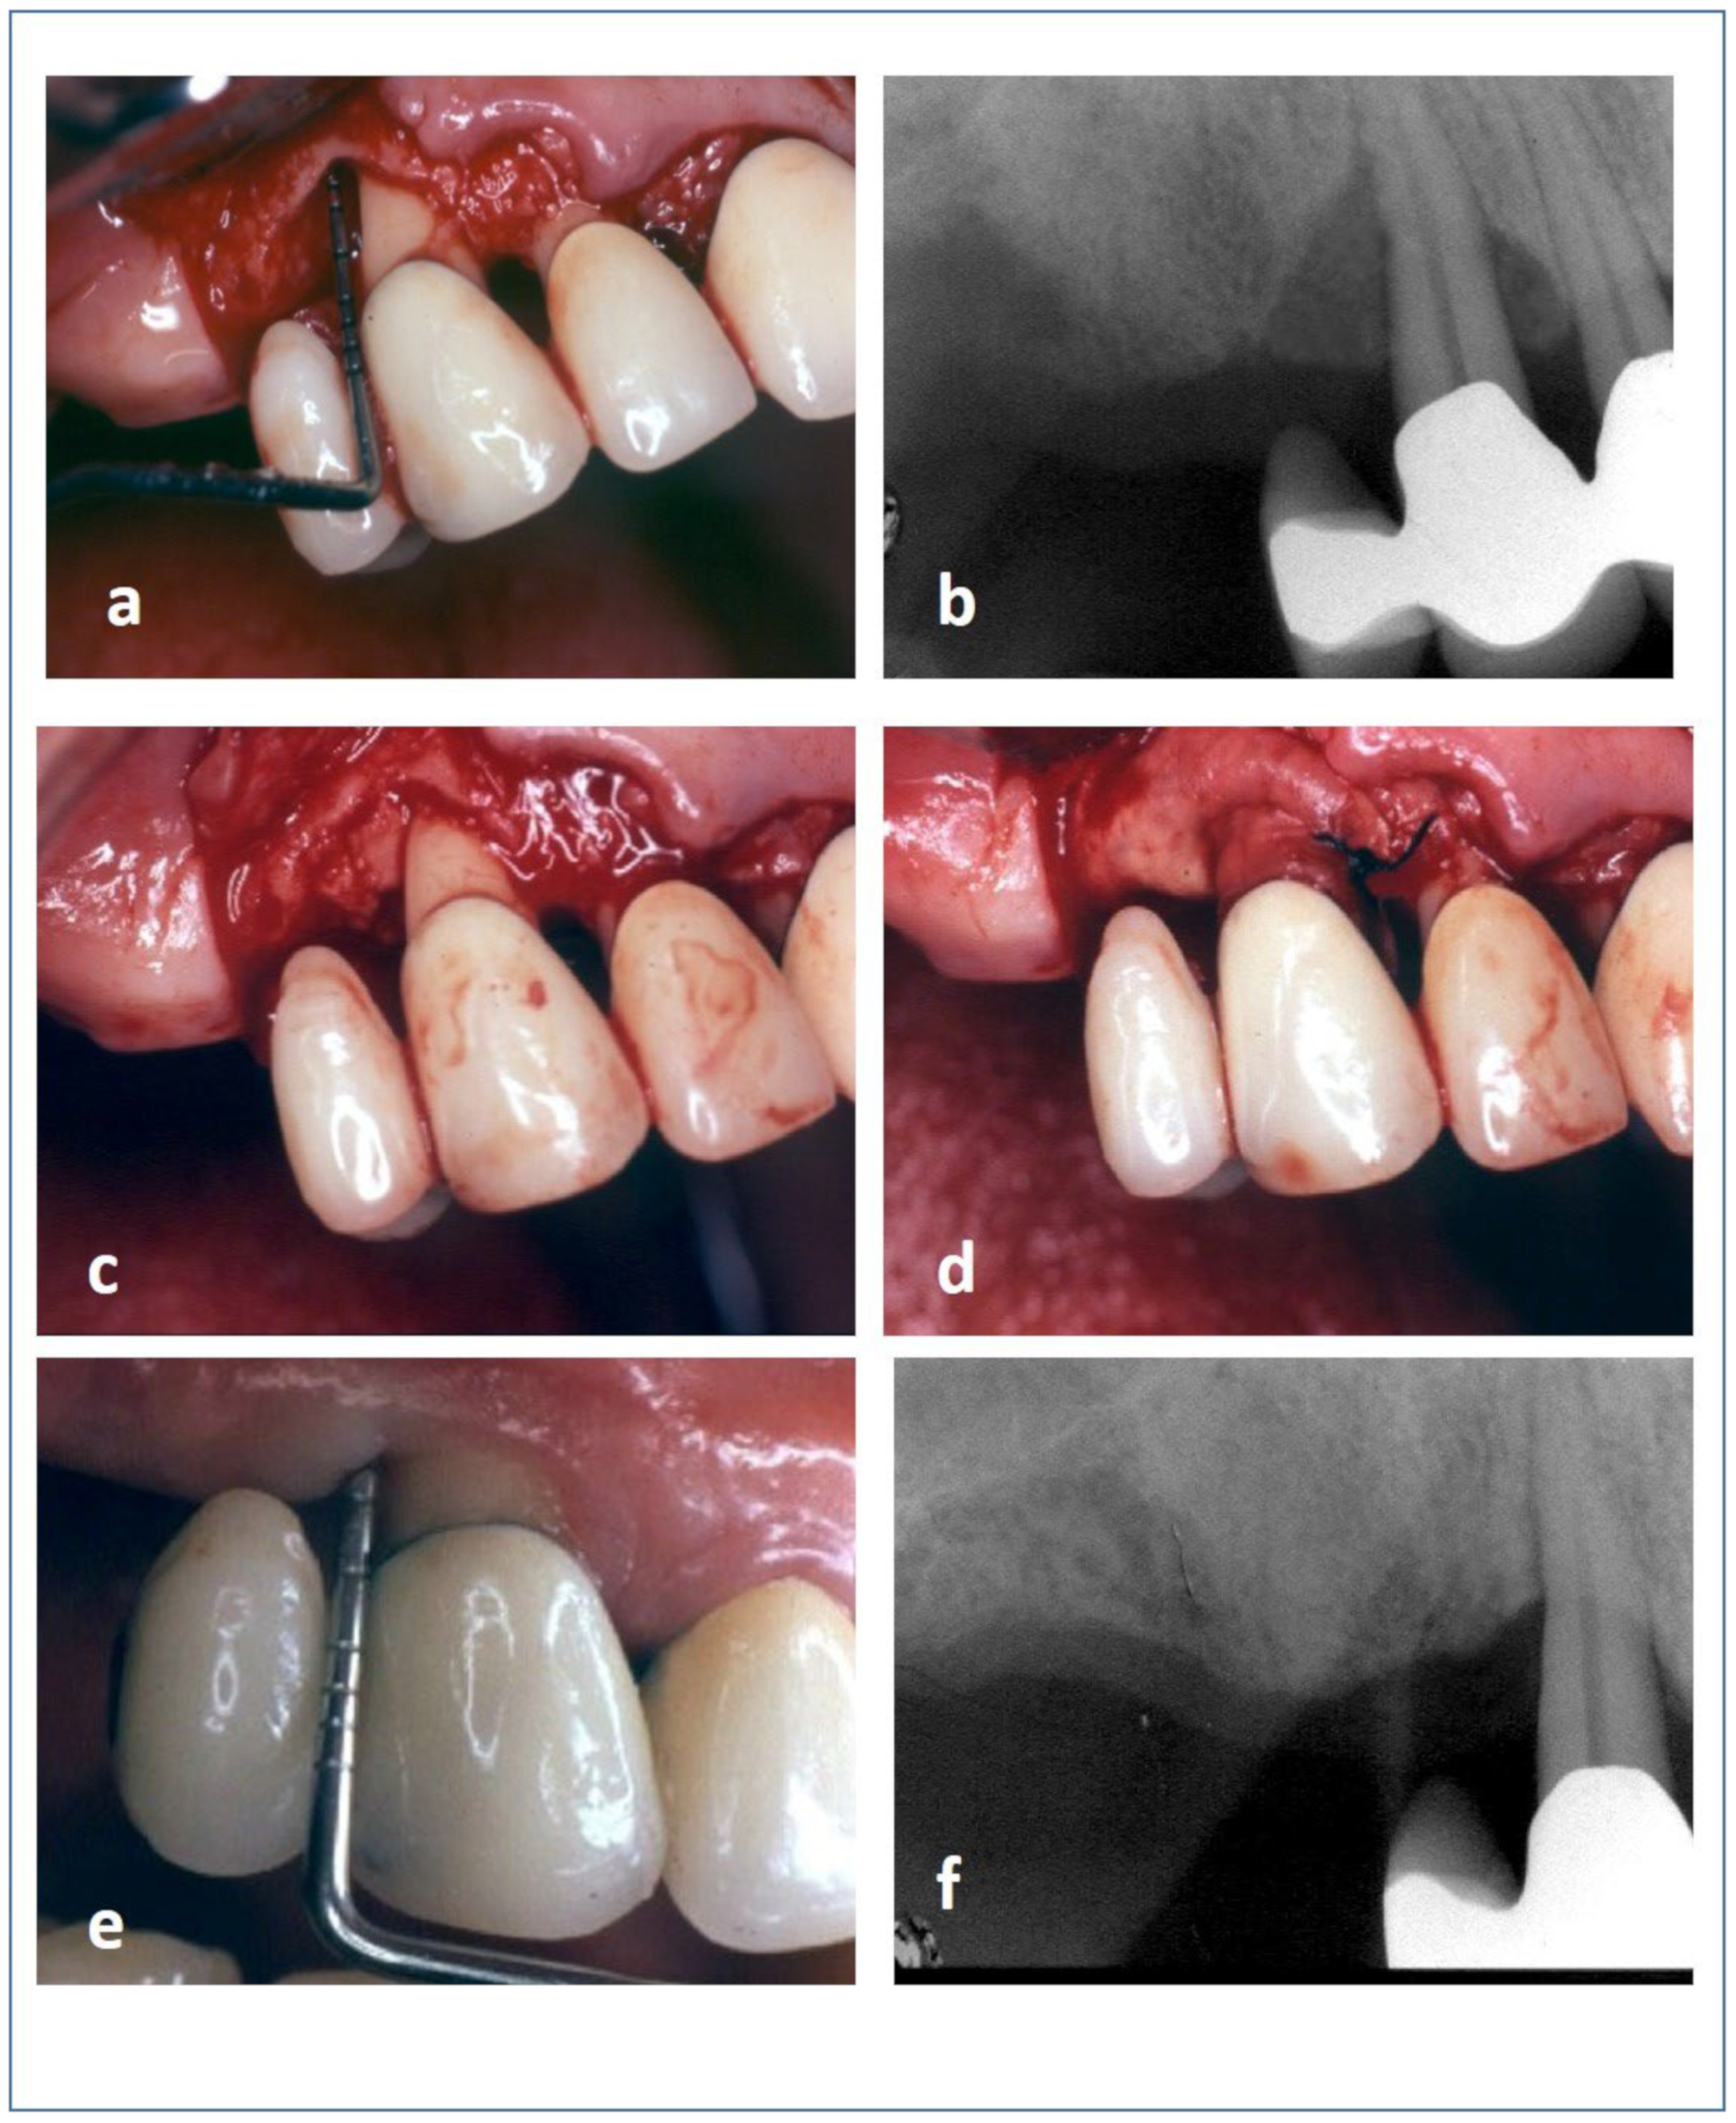

2.9. Surgical Procedure